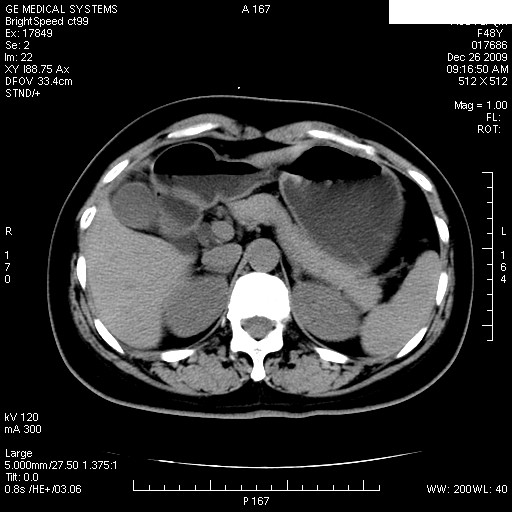

经过抗炎解痉镇痛治疗一周后复查ct如下:

1.图像看上去不是同一人(前组图像十二指肠未见明显异常,后组图像可见十二指肠占位)

2.后组图象印像

a.十二指肠球部前壁占位

b.坏蛆性胆囊炎,胆囊-结肠瘘(瘘口微小且时间较短,结肠内容返流入胆囊,形成胆囊壁钙化,胆囊内钙盐等沉积)

c.胆管炎,肝外胆管轻度扩张

坏蛆性胆囊炎,胆囊-结肠瘘,胆囊内钙盐等沉积.

1)肝内外胆管扩张,原因待查。2)胆囊内药物沉积?